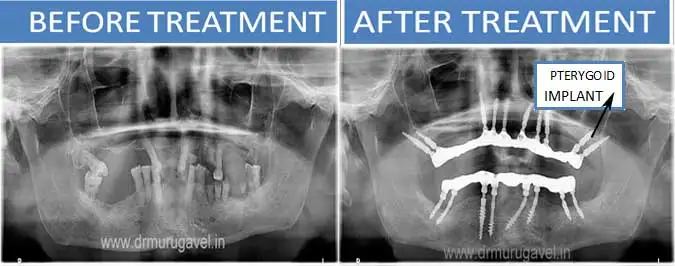

If you have been told by your dentist, that you have less bone or no bone in upper maxilla jaw, for dental implants, do not worry. These less bone situation can be successfully treated by pterygoid implants and fixed teeth can be given in 3-4 days.

Tubero pterygoid implants are indicated for patients who do not have enough bone for regular conventional implants. These implants are placed in the 2nd and 3rd molar region of the upper jaw.

– Avoids the need for sinus lift/bone grafts

– Helps to give fixed teeth in 3 days